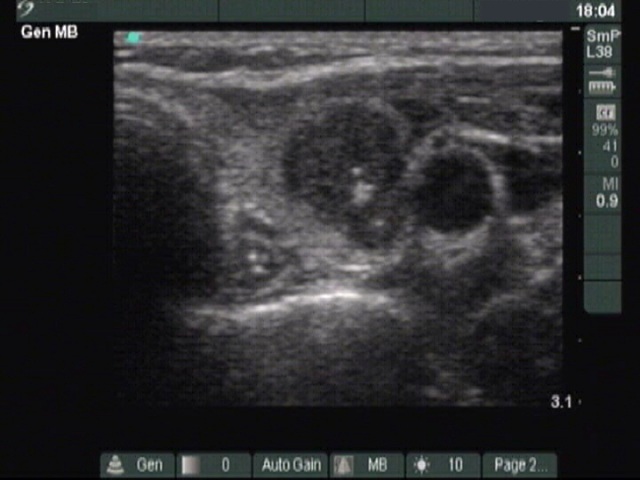

Medullary carcinoma (histological diagnosis) - case 529

A metastatic lymph node is presented in this case. The node has at least four hyperechogenic patches on the left in the horizontal scan. These have an echonormal background and display small hyperechogenic granules. There is acoustic shadow in the right in the longitudinal view.